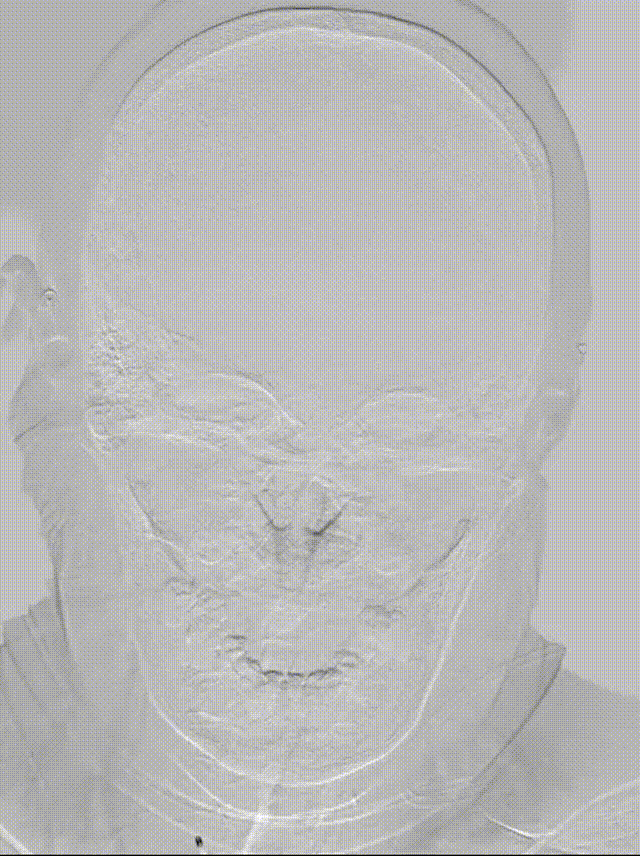

患者女性,83岁。

主诉:四肢无力伴言语不清4.5小时。

体格检查:嗜睡,构音障碍,肌力:左肢3级,右肢0级。NIHSS评分:24。

ECG: 心房颤动。